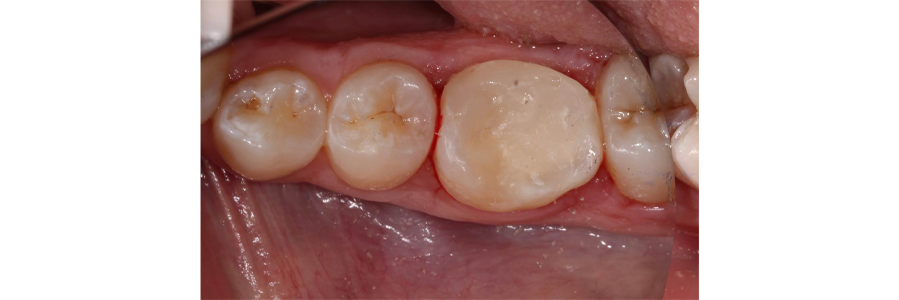

Hemostasis was achieved, and a bioceramic material was placed over the pulp exposure (Fig. 3) and the final restoration of composite was placed (Fig. 4).